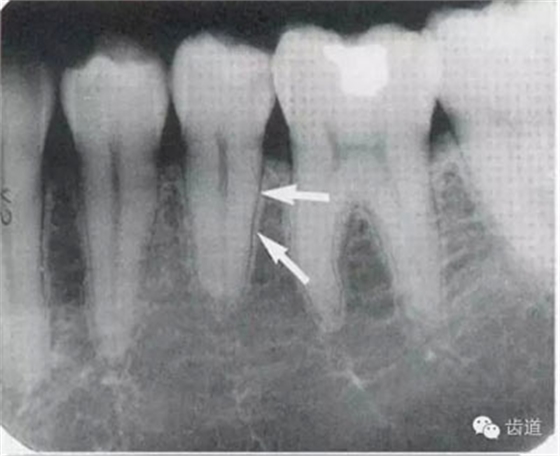

常見于下頜前牙區(qū),在牙根之間的牙槽骨內(nèi)并與牙長(zhǎng)軸平行的密度低的條狀影像。此為小血管進(jìn)入牙槽突的影像。